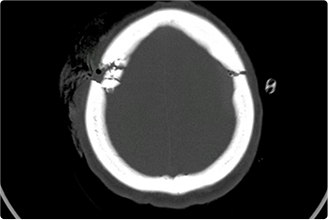

从事神经外科工作30年,擅长脑与脊髓血管类疾病、肿瘤、外伤等疾病的诊断与治疗,尤其擅长神经介入治疗各类脑血管疾病。累计完成介入栓塞颅内动脉瘤2000多例,颅内血管畸形数百例,夹闭颅内动脉瘤数百例,手术颅内与脊髓肿瘤数百例。在脑和脊髓血管病、肿瘤、外伤等方面有丰富的经验和较深造诣。

精通颅内动脉瘤介入栓塞和手术夹闭双技术,系统掌握脑动静脉畸形、颈内动脉海绵窦漏、硬脑膜动静脉漏等颅内血管疾病的诊疗和手术,精通颈动脉、椎动脉狭窄的血管内重建技术,以及颈动脉狭窄的内膜剥脱手术技术。在颅内肿瘤、椎管内肿瘤、颅脑损伤、高血压脑出血等疾病的诊治和手术,脑功能性疾病立体定向手术治疗等方面也积累了丰富的经验。

泰康仙林鼓楼医院神经外科副主任医师。中国卒中学会高级会员,复合介入神经外科分会高级会员。持国家卫健委神经介入资质证书(出血及缺血),中国抗癫痫协会中级专科医生证书,Global Neuro的创伤性脑损伤管理认证证书等。工作期间获得“泰康医疗十佳医生”、“泰康医疗新技术新项目”,及泰康仙林鼓楼医院“十佳医生”、“优秀感控”等荣誉。

擅长脑血管病(出血与缺血)的神经介入与微创手术,能熟练开展脑外伤、重度颅脑损伤的救治工作。